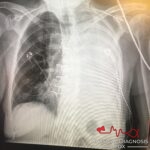

Patient 1:

This patient is a middle aged woman who presented with chronic cough. The finding is asymmetric chest expansion on inspiration. Her CXR shows a complete white out of her left lung. She had a large, malignant pleural effusion from a small cell lung cancer.